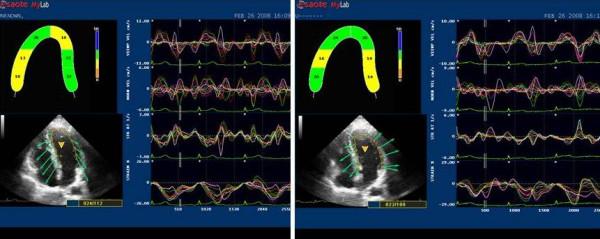

Ultrasound speckle tracking from grey scale images allows the assessment of regional strain derived from 2D regardless of angle intonation, and it is highly reproducible. The study aimed to evaluate regional left ventricular functional reserve in elite soccer players.

50 subjects (25 elite athletes and 25 sedentary controls), aged 26 +/- 3.5, were submitted to an echo exam, at rest and after the Hand Grip (HG) test. Both standard echo parameters and strain were evaluated.

Ejection fraction was similar in athletes and controls both at rest (athletes 58 +/- 2 vs controls 57 +/- 4 p ns) and after HG (athletes 60 +/- 2 vs controls 58 +/- 3 p ns). Basal (septal and anterior) segments showed similar strain values in athletes and controls both at rest (athletes S% -19.9 +/- 4.2; controls S% -18.8 +/- 4.9 p = ns) and after HG (athletes S% -20.99 +/- 2.8; controls S% -19.46 +/- 4.4 p = ns). Medium-apical segments showed similar strain values at rest (athletes S% -17.31 +/- 2.3; controls S% -20.00 +/- 5.3 p = ns), but higher values in athletes after HG (athletes S% -24.47 +/- 2.8; controls S% -20.47 +/- 5.4 p < 0.05)

In athletes with physiological myocardial hypertrophy, a brief isometric effort produces enhancement of the strain in medium-apical left ventricular segments, suggesting the presence of a higher regional function reserve which can be elicited with an inotropic challenge and suitable methods of radial function quantification such as 2D-derived strain.

基于灰阶图像的超声斑点追踪技术能够评估二维区域应变,不受角度影响,且具有高度可重复性。本研究旨在评估精英足球运动员的左心室区域功能储备。

50名年龄为26±3.5岁的受试者(25名精英运动员和25名久坐不动的对照组)接受了静息状态下和握力(HG)试验后的超声心动图检查。评估了标准超声心动图参数和应变。

运动员和对照组在静息状态下(运动员58±2 vs对照组57±4,p无统计学意义)和HG试验后(运动员60±2 vs对照组58±3,p无统计学意义)的射血分数相似。基底段(室间隔和前壁)在运动员和对照组静息状态下(运动员S% -19.9±4.2;对照组S% -18.8±4.9,p无统计学意义)和HG试验后(运动员S% -20.99±2.8;对照组S% -19.46±4.4,p无统计学意义)的应变值相似。中尖段在静息状态下应变值相似(运动员S% -17.3±2.3;对照组S% -20.0±5.3,p无统计学意义),但在HG试验后运动员的应变值更高(运动员S% -24.47±2.8;对照组S% -20.47±5.4,p<0.05)。

在生理性心肌肥厚的运动员中,短暂的等长运动可使左心室中尖段的应变增强,提示存在更高的区域功能储备,这种储备可通过正性肌力刺激和合适的径向功能量化方法(如二维应变)激发。